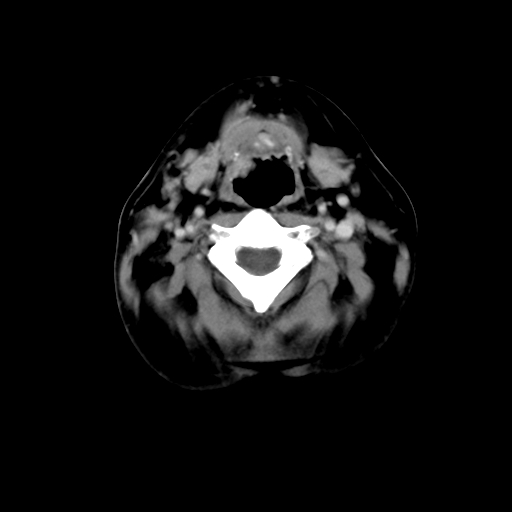

标题: CT24019:男,45岁,发现颈部肿物5个月。 [打印本页]

男,45岁,发现颈部肿物5个月,彩超示:双侧颈部及下颌部软组织增厚。

考虑双侧颈项部良性对称性脂肪增多症。